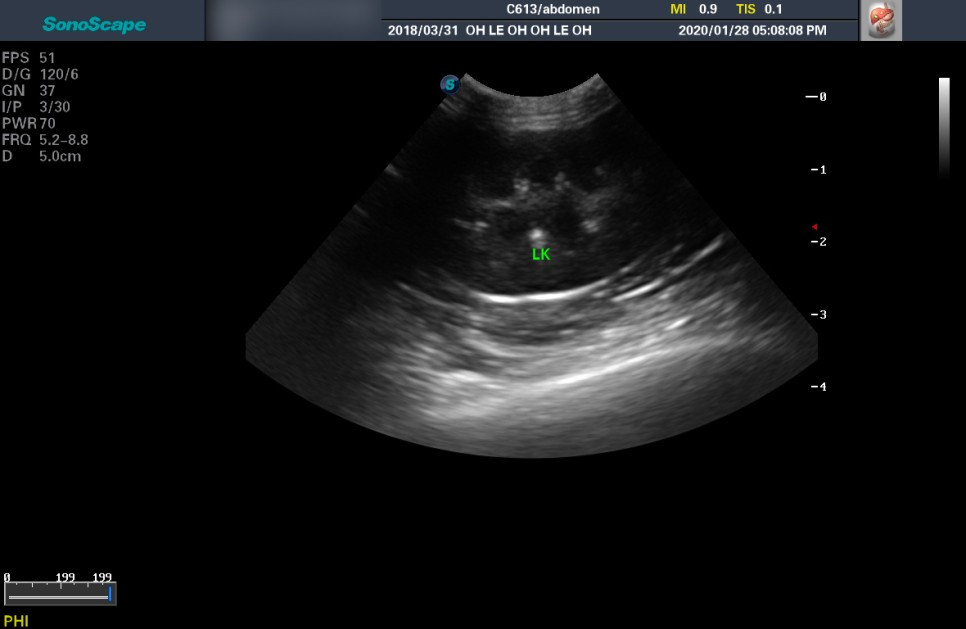

중성화 수술을 보냈을 때 들었던 복부 결절의 정체가 궁금해 여쭈었다. 흰 실타래가 엉켜있는 것 같은 모양의 염증 덩어리가 보였다고 전해 들었던 것을 말씀드렸다. 일단 복부 초음파와 X-ray를 찍어보자고 하셨다.

X-ray 상에서 다행히 복수는 없었다. 전체적인 염증은 아니라는 뜻이다. 하지만 동그란 결절이 여러 개 나왔는데, 정확하게 무엇인지는 알 수 없다고 하셨다. 아마 이것이 수술할 당시에도 보였던 것일 결절일터였다. 초음파까지 시행했는데 초음파 상에서도 비정상적인 소견은 없었다. 동그란 결절들은 초음파에선 보이지 않았다.

장 근처에 보이는 둥근 결절들